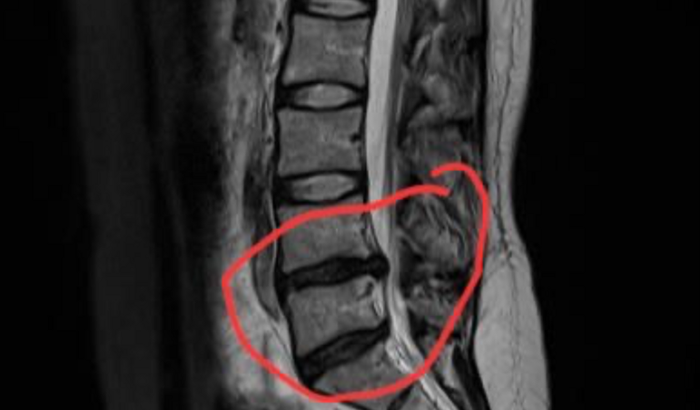

Há mais de 60 dias, estou praticamente presa à cama por conta de uma hérnia de disco severa. A dor é incapacitante – não consigo sentar, andar direito ou realizar tarefas simples. Depois de tentar diversos tratamentos sem sucesso, a única solução agora é a cirurgia.